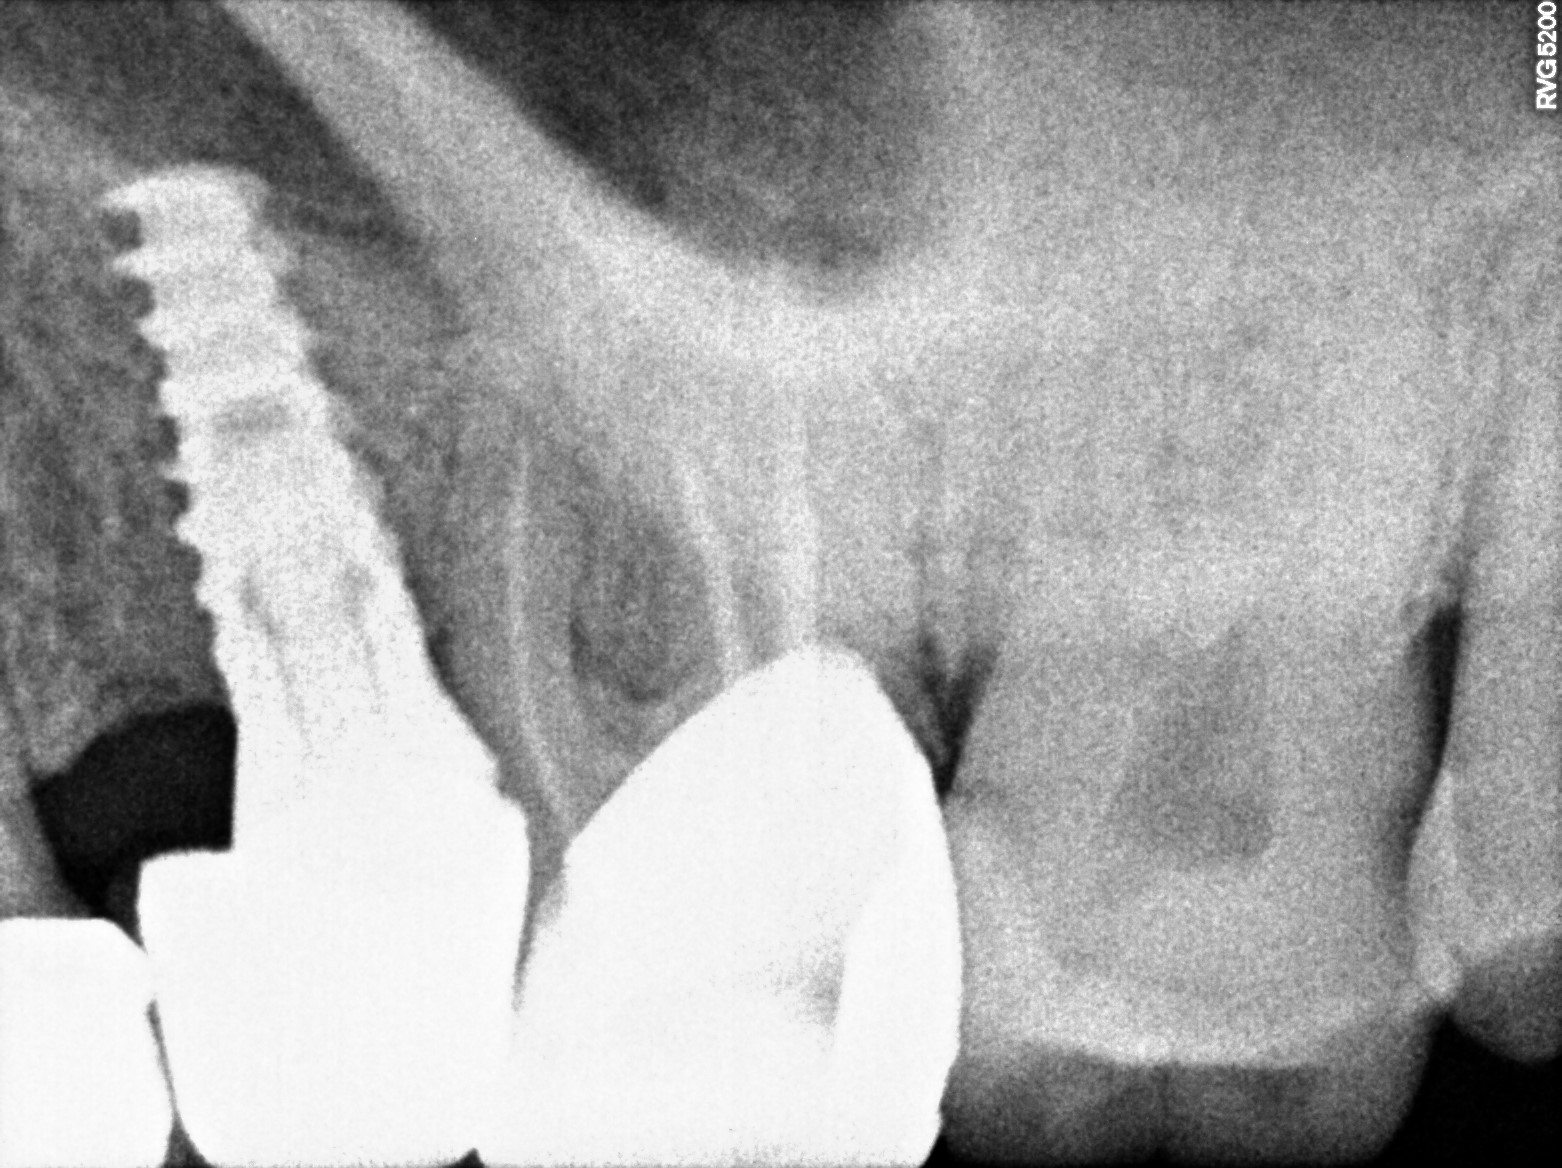

Dental Radiographs FHIR: DocumentReference · LOINC 24641-7

R53 (2).jpg

24641-7